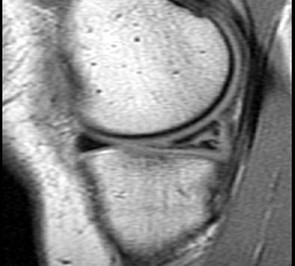

问题 男,29岁,左膝关节有外伤史,膝关节疼痛,活动受限,请结合所提供的图像,选择最佳选项 ( )

选项 A、内侧半月板内侧撕裂 B、后十字韧带撕裂 C、前十字韧带撕裂 D、内侧半月板外周后角垂直撕裂 E、未见异常

答案 A